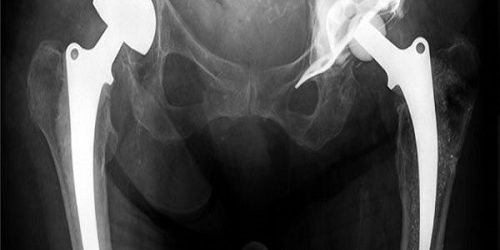

Cerrahi Müdahale: Asetobuloplasti işlemi, genellikle genel anestezi altında gerçekleştirilir. Cerrahi ekip, asetabulumun kırık veya deformiteli bölgesini düzeltmek için gerekli olan kesileri yapar ve kemikleri yeniden şekillendirir veya sabitleyici implantlar kullanarak sabitler.

Cerrahi Müdahale: Ağır ve/veya deplase (kemiklerin yerinden kayması) kırıklarda cerrahi müdahale genellikle gereklidir. Cerrahi müdahale sırasında kırık kemiklerin yerine getirilmesi ve uygun pozisyonda sabitlenmesi sağlanır. Bu genellikle plakalar, vida veya diğer cerrahi implantlar kullanılarak yapılır.